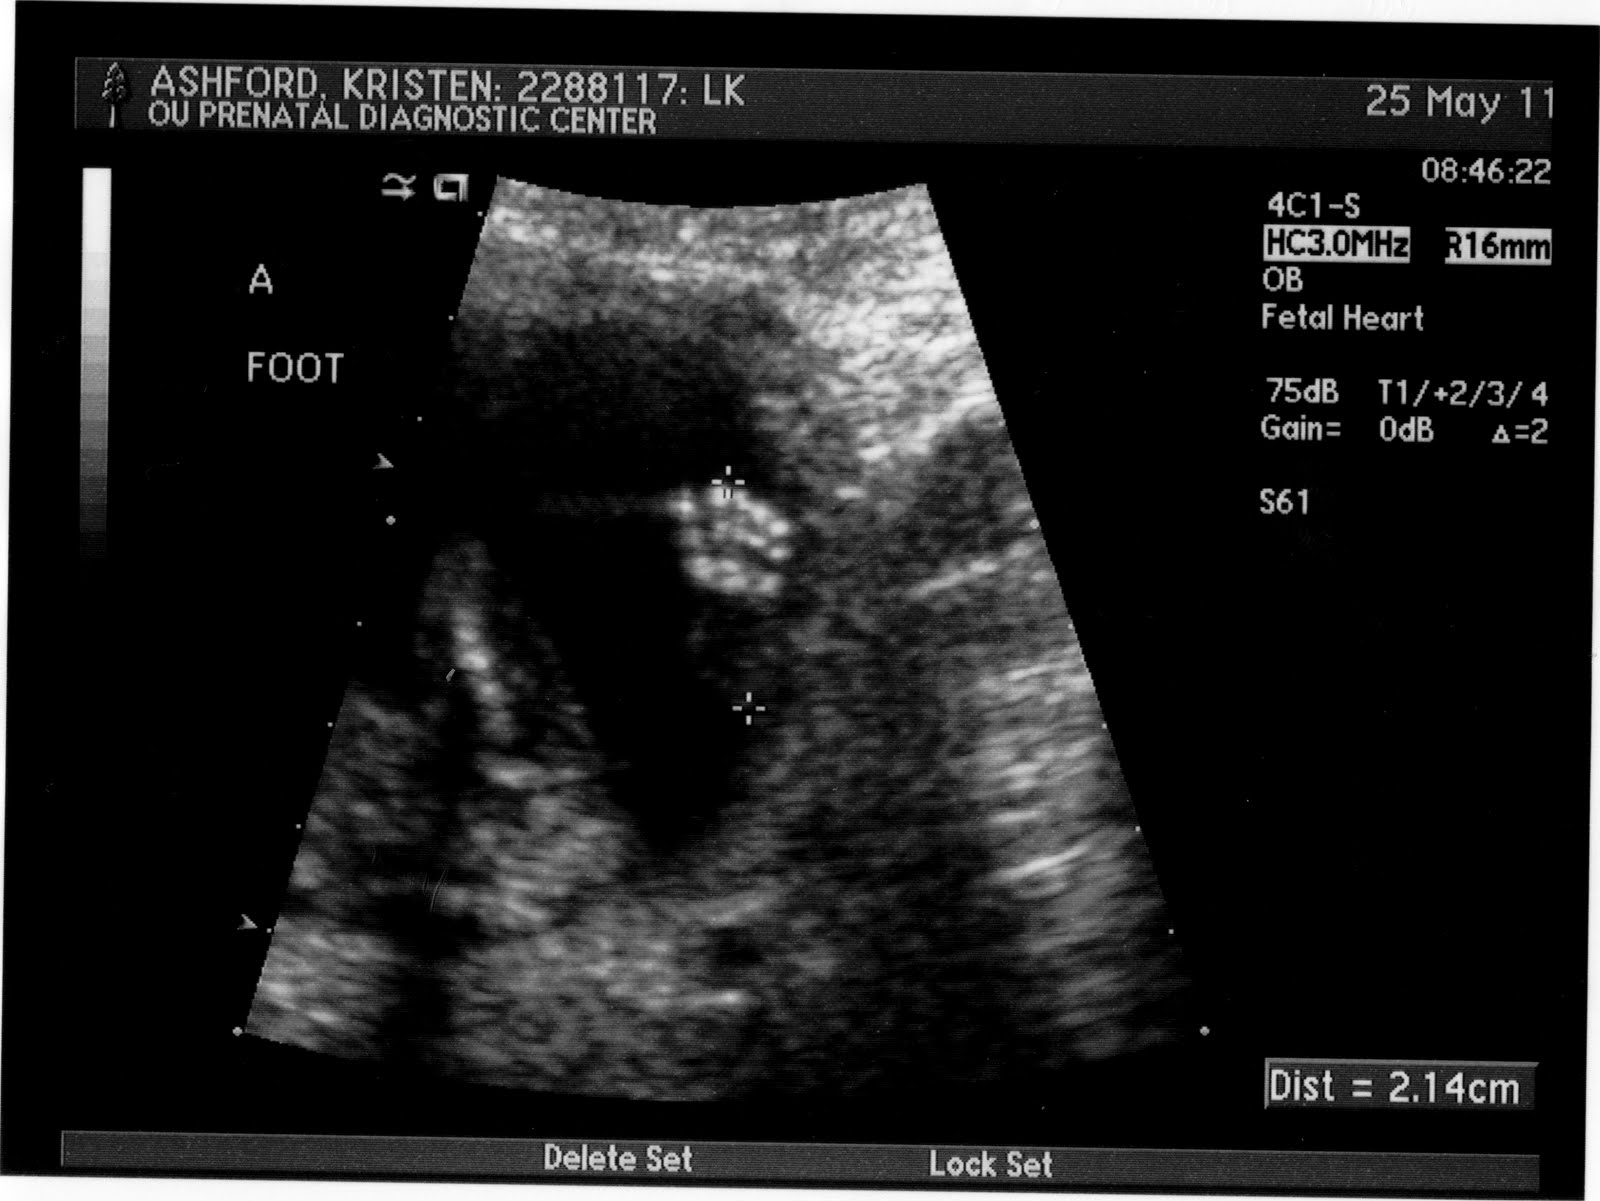

We had such a great appointment today! The ultrasound tech was wonderful and described everything she was doing and the measurements she was taking. We got to watch it on a flat screen while she did the ultrasound and it was just amazing. Oh how fearfully and wonderfully made they are! Thank you Lord! Oh how I just loved seeing their little hands and feet and I just can't wait to kiss them! The ultrasound tech was able to see the genders and we saw that they were girls!! We were pretty surprised! I was totally thinking that they were boys, but what a fun surprise! The girls were measuring well with one measuring 16 weeks, 1 day and the other measuring 16 weeks 2 day. They both weighed 6 ounces! Praise God!

And without further ado, some pictures of our two youngest little girls:

Baby A profile

Baby B profile